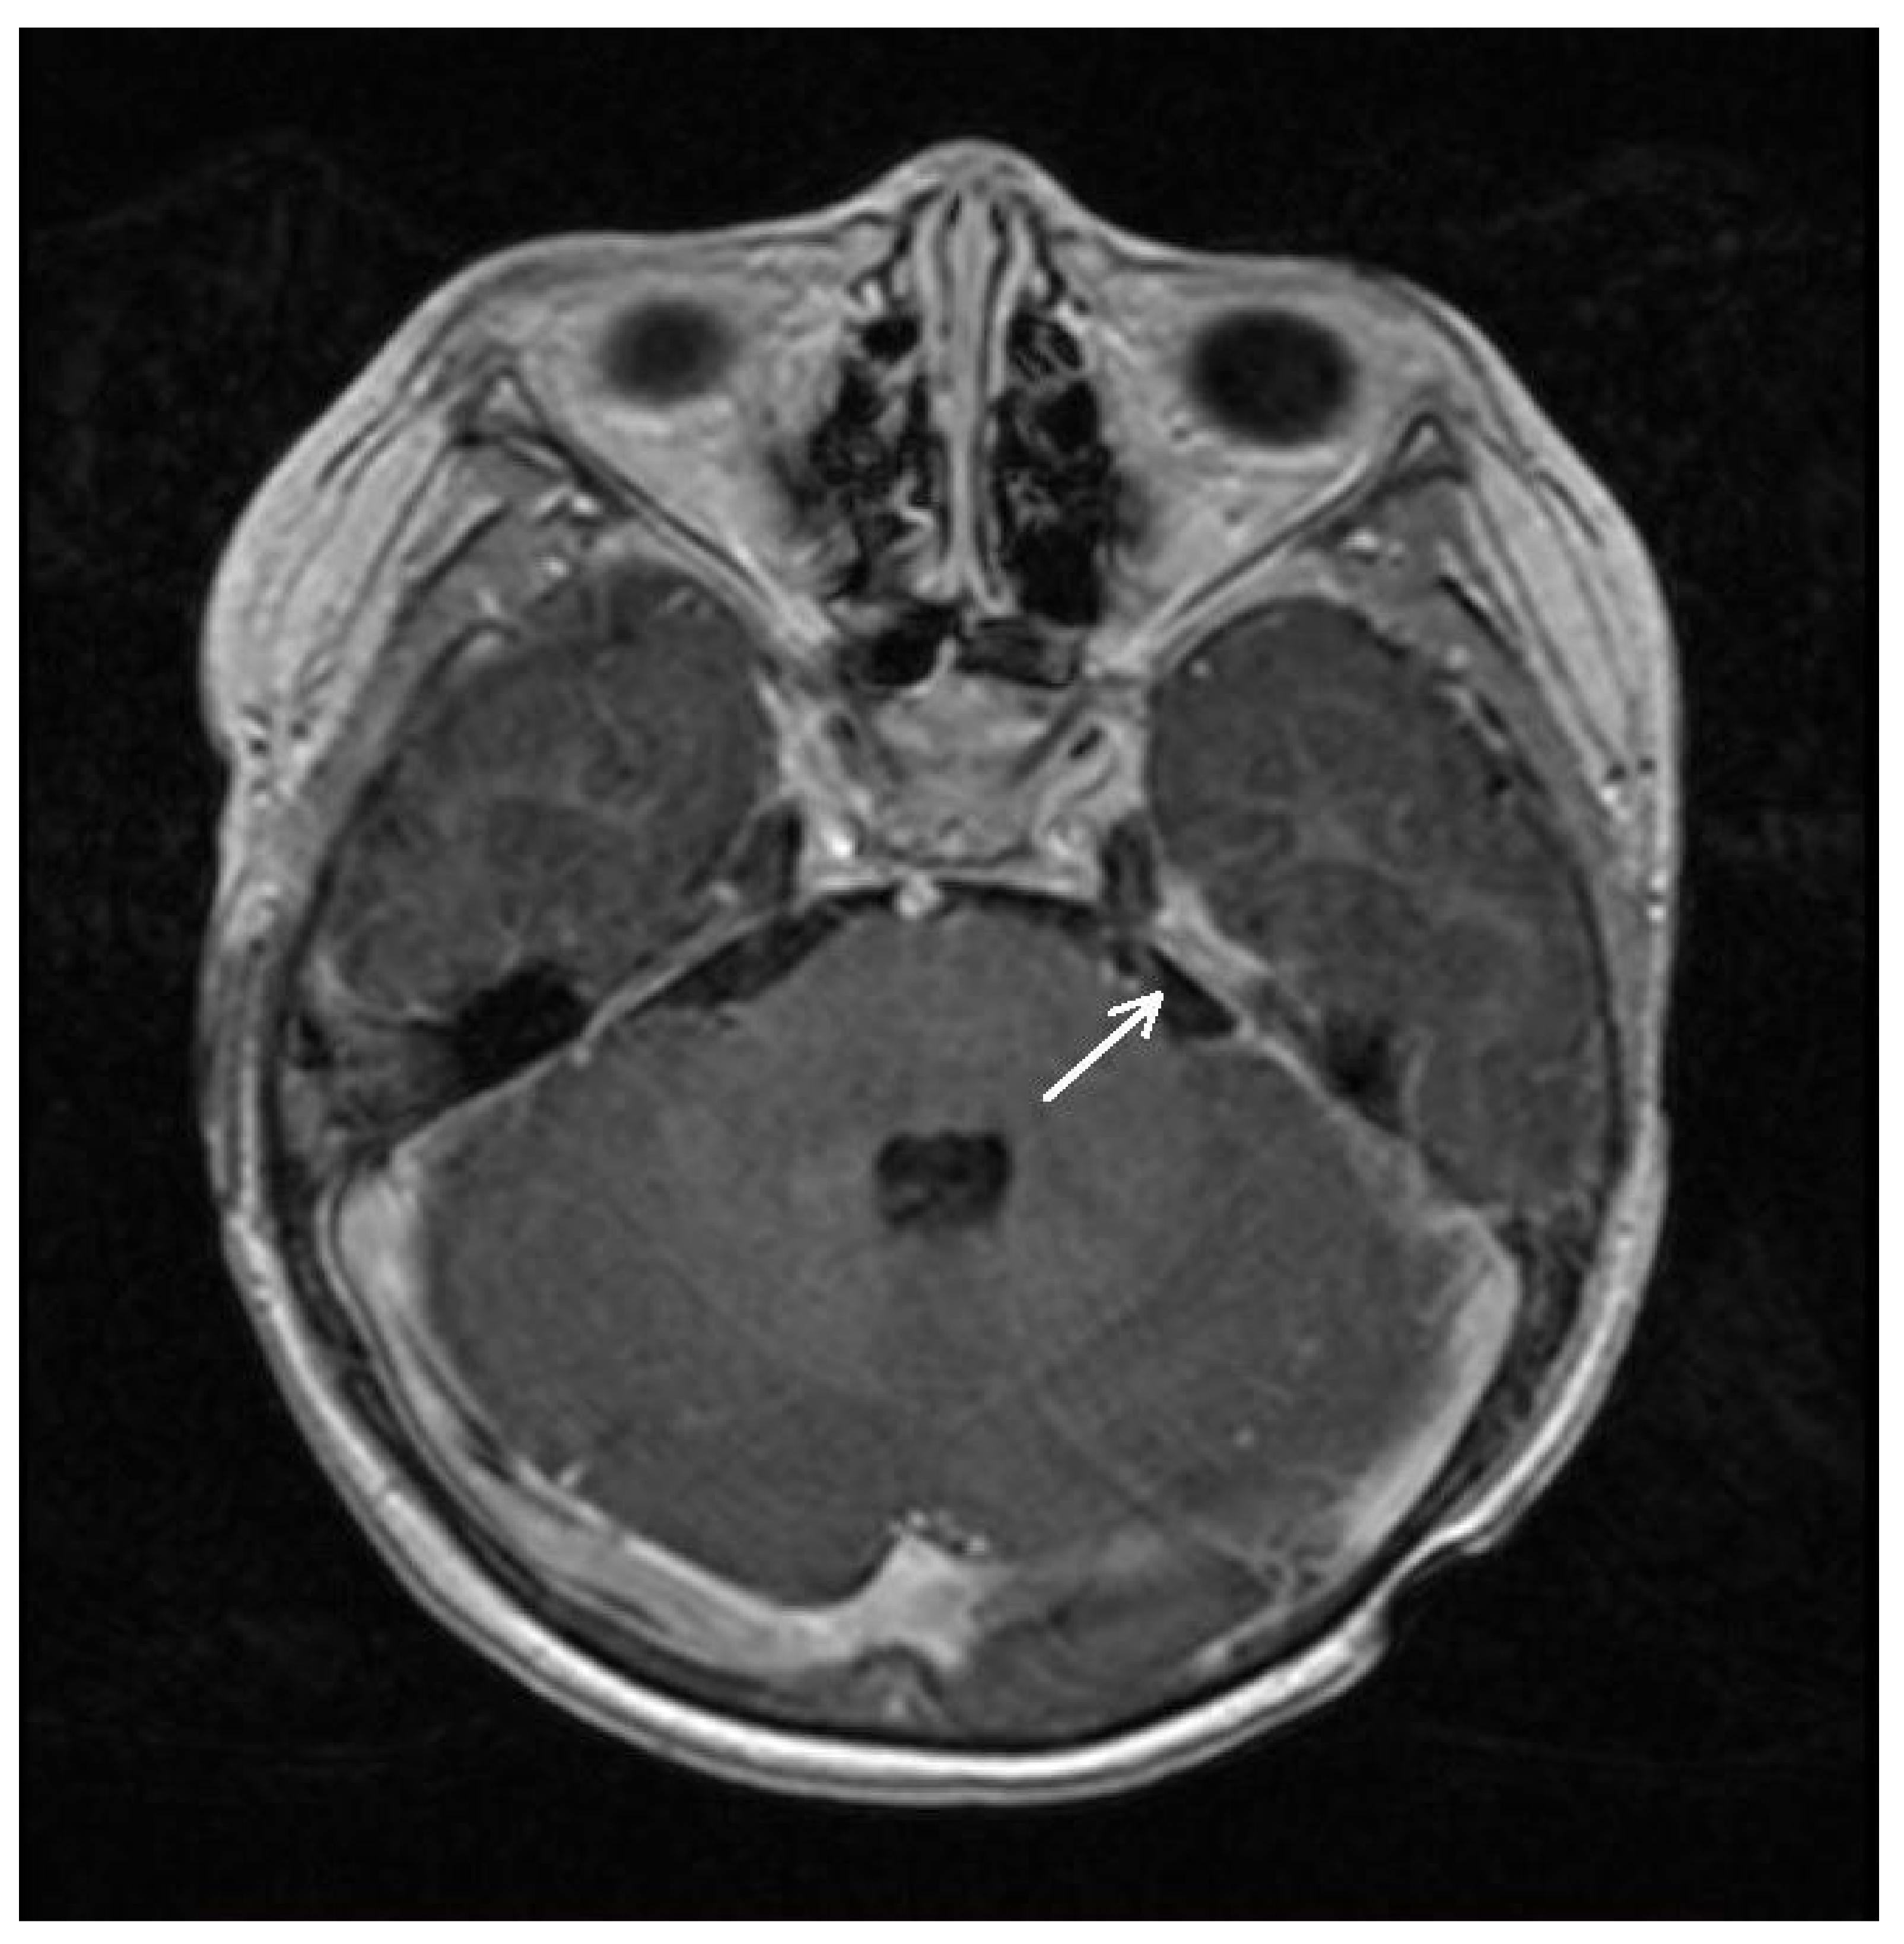

| 8 January 2021 | Spinal MRI (T9-S4 mass: 39 × 36 × 205 mm; & C1-C2 mass: 7.4 × 6.2 mm; Figure 1A) Brain MRI (leptomeningeal metastasis of the left temporal lobe: 25 × 5.5 mm) |